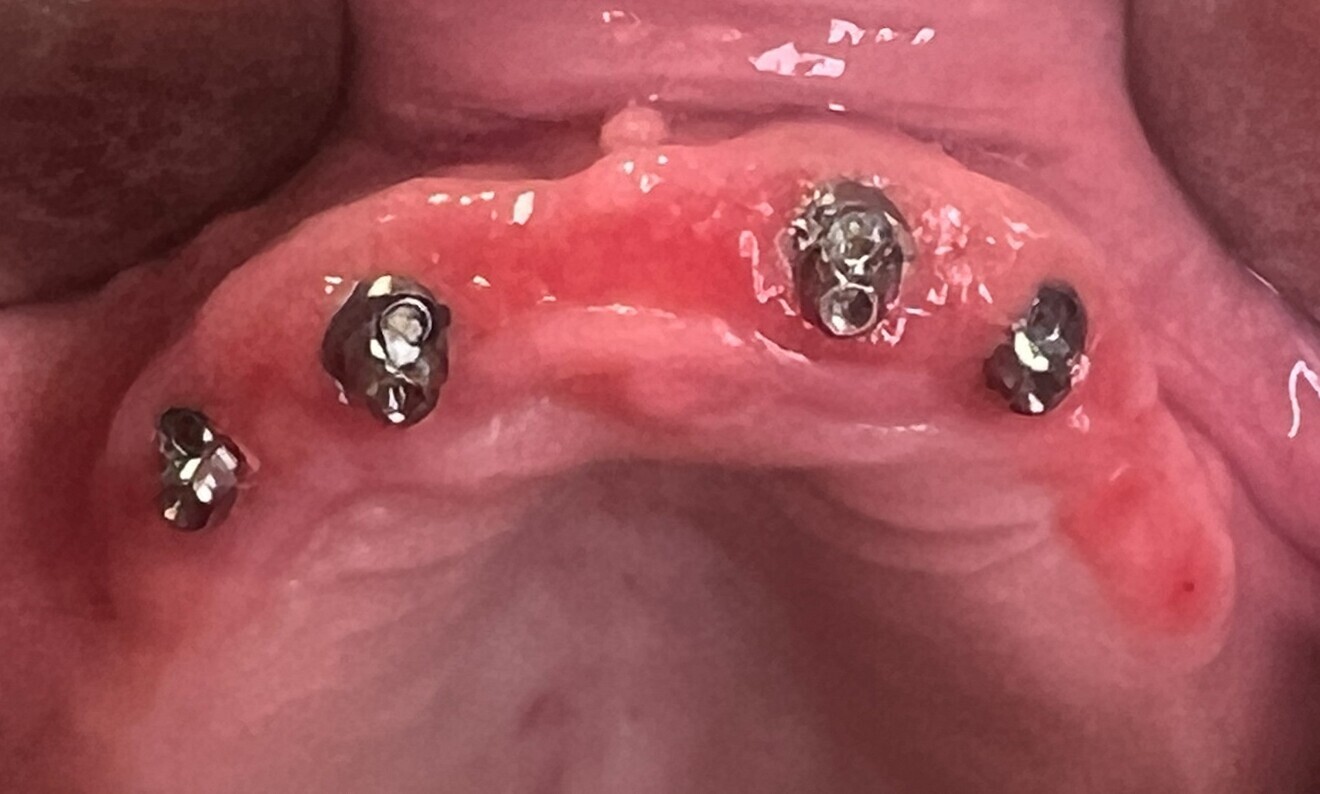

Fig. 3: Areas of chronic inflammation of transmucosal tissue evident after removal of the maxillary prosthesis.

A 75-year-old female patient in good mental and physical health presented with an implant-supported denture in the maxillary arch with widespread peri-implantitis and burning mouth syndrome (Figs. 1–3). In the lower jaw, she presented with a removable complete denture, abraded teeth and incongruence between the base and alveolar process. The patient reported pain and bleeding in the maxillary arch with compromised stability of the mandibular denture.